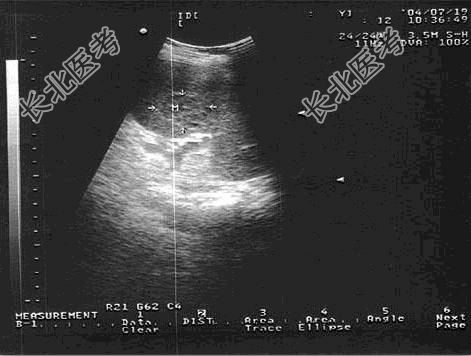

- [材料题] 女,19岁,有淋巴瘤病史。结合超声检查如图。

- 简答题1、该病患考虑诊断为 ?

- 简答题2、脾淋巴瘤的超声表现有哪些?